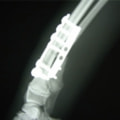

トイプードル 右遠位橈尺骨短斜骨折のALPSによる内固定

Locking Compression Plate

LCPは、スクリュー(ネジ)とプレート(金属の板)をロックする特殊な構造により骨折部位を固定する新しい世代のプレートシステムです。ひとつのホールでロッキングスクリューとスタンダードスクリューの使用を選択できるユニークな構造をしているため、骨折断端間の圧迫を目的とした従来型プレート固定法に加え、高い角度安定性を有するロッキングスクリューを用いた固定法の選択が可能です。従来のプレートシステムでは困難だった部分の骨折や癒合不全の症例に高い治療効果をもたらします。